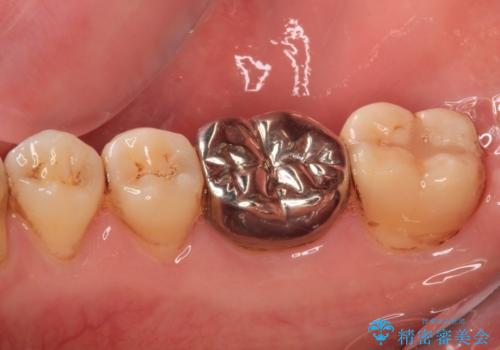

- 人と話す際に、下顎の奥にある銀歯が目立って気になるとのことで来院された患者様です。

左右の奥歯に銀歯のクラウンが装着されていたため、銀歯除去後に仮歯に置き換え、フルジルコニアクラウンにて補綴治療を行うこととしました。